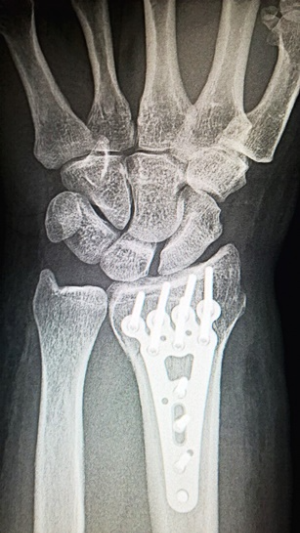

수술적 치료는 보존적 치료로 증상 개선이 이루어지지 않거나 증상이 심각한 경우에 시행됩니다. 이 방법은 손목 터널 증후군 치료에서 가장 확실한 효과를 보여줍니다. 수술적 치료는 신경을 압박하는 원인을 직접 제거하는 방식으로, 인대를 절개하여 압박을 완화합니다. 과거에는 손목 전체를 절개했지만, 최근에는 관절경을 사용하여 국소부위만 절개하는 방식이 주로 사용되어, 수술 시간이 단축되고 회복기간도 더 짧아졌습니다.